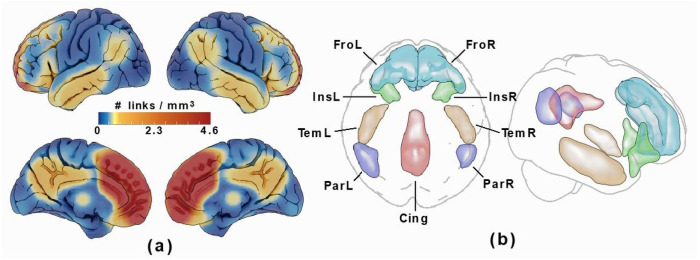

A medial frontal lobe region of interest (ROI) was created for each hemisphere using the Schaefer 200 parcel 7 network atlas (ref. Schaefer, Kong et al. 2018). Selected parcels were those overlapping the predicted location of the PCS in MNI-152 space (ref. Grabner, Janke et al. 2006). ROIs are detailed in Supplementary Figure 1.

Voxel wise whole brain connectivity in 6 × 6 × 6 mm3 space was evaluated using a two-step procedure. First the mean connectivity of all voxels was calculated using Persons r correlation.

The functional connectome was then restricted with a network mask corresponding to high connectivity with the medial frontal lobe ROIs by thresholding the all-subject-mean connectivity of all subjects at a correlation corresponding to P = 0.0001 (given the number of frames in the rs-fMRI time series). Cortical ROIs corresponding to this network mask, which included the bilateral anteromedial frontal cortices as well as portions of the insular, lateral temporal, parietal, and posterior cingulate cortices were then drawn on the resulting voxel-wise link density maps, see Figure 3. These regions are part of the DMN and SN resting state networks, which both overlap with the source region. As scattered connectivity was obtained with subcortical regions of the basal ganglia and hippocampus/amygdala, these structures were added to the ROI set using the anatomical definitions according to the Harvard-Oxford subcortical atlas (ref. Desikan, Ségonne et al. 2006) and not by manual delineation. Note that the tracing of these regions only affected the visualization and labelling in the resulting connectograms and that the network mask used in the calculation was applied to the links and not the voxels.

Voxel-based Functional connectivity

Two individuals were excluded from analysis as they did not have available handedness data. Voxel based functional connectivity analyses were performed for 127 individuals. The only significant component was identified in individuals possessing a left PCS relative to individuals with an absent left PCS at P = 0.01, controlling for family wise error rate. Results are displayed in Fig. 4. The greatest link density was found converging on the left anterior cingulum, extending inferiorly towards the frontal medial orbitus and the right anterior cingulum. More extended connections were also found to the frontal superior medial gyrus, the left and right posterior cingulum, as well as scattered connections to subcortical structures including the left amygdala, the right posterior hippocampus, and left thalamus.

We identify that the medial frontal lobe ROI corresponding with the location of the PCS is highly connected to regions of the cingulum, insula, frontal, temporal, and parietal cortex as well as the thalamus, caudate, pallidum, putamen, hippocampus, and amygdala, key components of the DMN and SN, in accordance with standard literature (ref. Catani and Thiebaut de Schotten 2012). In the left hemisphere large-scale connectivity changes were observed revealing a significant network component with greater rsFC in individuals with an absent left PCS relative to those with a present left PCS. This component comprised the left and right anterior cingulum and frontal medial orbitus with more extended connections to the left and right frontal superior medial gyrus and the posterior cingulum, as well as scattered connections to subcortical structures; the left amygdala, the right posterior hippocampus, and left thalamus. The increase in connectivity identifies alternate functional architecture in individuals with an absent left PCS, where distributed network nodes are enlisted creating an alternate specialisation profile with auxiliary processing power drawn from more distal regions outside of the anterior cingulate. Again, with consideration of the findings from the tract segmentation analyses a more dispersed network as identified in individuals with an absent PCS, may become operational where a highly localised network (presumed to exist where a PCS is present) is not present. In turn, cognitive advantages reported in the literature (ref. Fornito, Yücel et al. 2004, Whittle, Allen et al. 2009, Borst, Cachia et al. 2014, ref. Cachia, Del Maschio et al. 2017) associated with the presence of a left PCS may be underpinned by an efficient highly localised network dependent on U-fibres rather than a well organised cingulum bundle. These observations are in line with and provide further evidence for the tension-based morphogenesis theory of cortical folding (ref. Van Essen 1997) and support the notion that well interconnected brain regions display strong patterns of functional connectivity (ref. Segall, Allen et al. 2012) (ref. van den Heuvel, Stam et al. 2009). Extending this concept to disease, we speculate that a highly connected localised network existing in the presence of a PCS may account for the resilience to disease expression observed in individuals with a right PCS in bvFTD and explain why absence of a left PCS, a neurodevelopmental aberration, has been associated with schizophrenia and OCD (Harper, Lindberg et al. 2022) (ref. Amiez, Neveu et al. 2013, ref. Harper, de Boer et al. 2023) (ref. Yücel, Stuart et al. 2002) (ref. Shim, Jung et al. 2009). Studies exploring these hypotheses in these disease groups are indicated in order to provide evidence for this theory. Furthermore, it is known that AC gyral variability affects gyral volume and thus should be taken into account in the study of relevant diseases (ref. Fornito, Whittle et al. 2006). Here we demonstrate that this is also the case for structural anatomy.